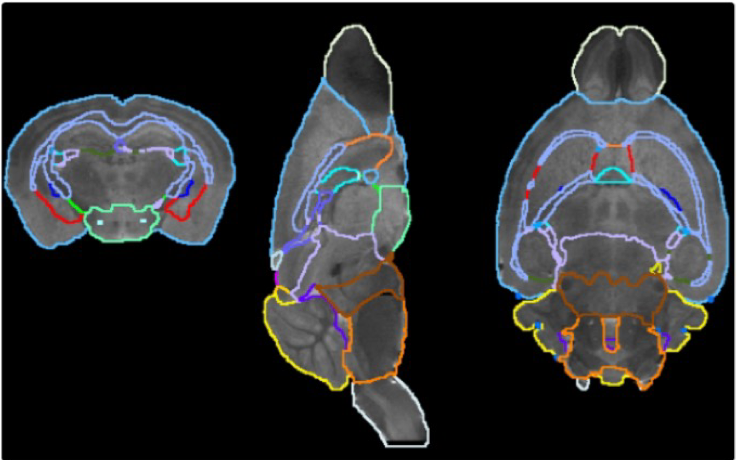

pmod’s tools provide comprehensive workflows for post-processing and quantification of imaging data for fundamental oncology research, development of radiotracers and theranostics, and in clinical research studies. Imaging scientists can trust pmod to reproducibly read their data, interpret the meta-data/units and help users calculate statistics such as SUV for their studies and publications.

• Multimodality segmentation tools – comprehensive semi-automated and manual tools for precision and reproducibility